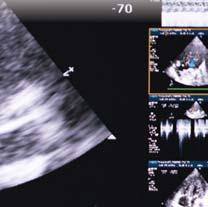

At the crossroad of every medical department is the need for imaging. Whether monitoring disease progression, assisting with diagnoses, or providing insight through important clinical trials, the UC Department of Radiology is at the center. In fact, these international leaders in stroke and brain health are involved in more than 200 clinical trial sites around the world—designing studies, providing quality control, interpreting imaging data, and working with statistical teams to answer questions. It’s forward indispensable medicine,